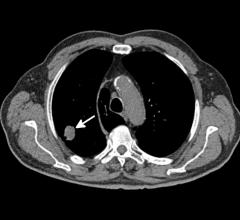

A 26-year-old man with history of diabetes and hypertension presented with 7 days of fever, chills, nausea, intractable ...